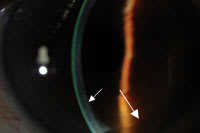

Full illumination (top) and slit beam (bottom) photos of a DSEK eye 3 months after surgery. The full illumination image indicates the graft clarity and absence of any sutures. The large arrows indicate the edge of the graft. The slit beam illuminates the donor tissue behind the recipient cornea, and the small arrow indicates the interface between the donor and recipient. |